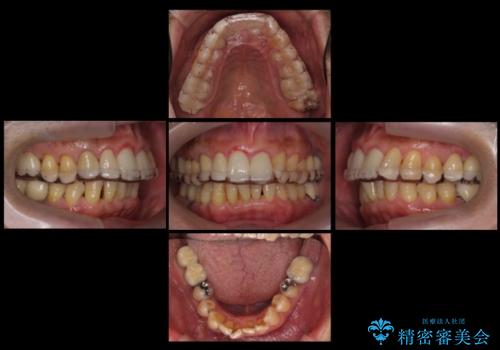

また、向かい合う上の歯が挺出(伸び出してしまうこと)しており、インプラントを入れることが難しかったため、長さを短くかぶせ治しました。

また、上顎前歯以外の根の治療のやり直しを行いました。

左下に関しては、経過観察を行い、歯が割れたりした場合にインプラントを考えることになりました。

セラミックが欠けるのを防ぐため、また、左上7は対合歯がなく挺出してしまうのを防ぐため、ナイトガードを就寝時に装着していただいています。

大臼歯の再根管治療は、銀座院院長の林先生にお願いしています。